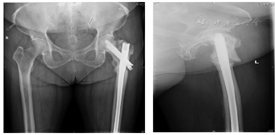

1.2013年5月双髋关节正侧位X线片显示左侧股骨颈骨折,GardenII型(图1)。

2.2015年12月双髋关节正侧位片显示左侧股骨颈骨折已愈合,发生颈吸收、颈短缩,空心钉退钉(图2)。

3.2016年3月 患者取出一枚空心钉后,再次跌倒,发生左侧股骨粗隆下骨折。在骨折远端边缘有鸟嘴样皮质增厚改变,此为股骨不典型骨折的特征表现(图3)。